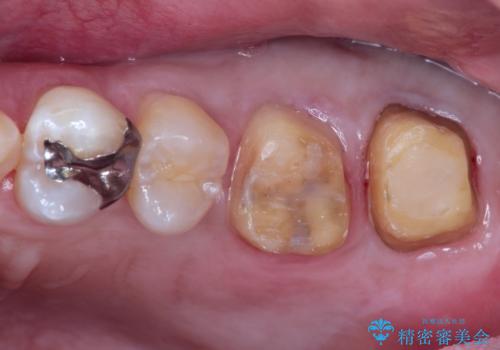

目立つ金歯を自然な色のオールセラミックへ

- 矯正の治療後に目立つ金歯を白くしたいとのことで治療することとなりました。

左上の奥歯に大きな金歯と、その後ろの歯が矯正治療用の仮歯が装着されていました。

これらの歯にオールセラミッククラウンを装着することとなりました。